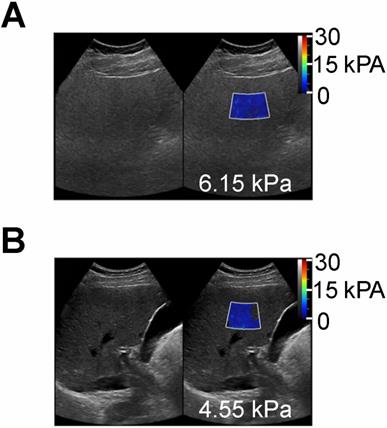

Figure 4

Shear wave elastography quantitative ultrasound method with calculated SWE measurements shown as color-coded scale superimposed on grayscale clinical images. (A) 55 year old female patient with NAFLD and MRI calculated fat fraction of 43 % with SWE measurement of 6.15 kPa and (B) a 60 year old male without history of NAFLD and MRI calculated fat fraction of 1.4 % with SWE measurement of 4.55 kPa. These SWE measurements show no significant differences (6.15 vs 4.55 kPa) despite marked variability in MR calculated fat fractions (43 % vs 1.4 %).”